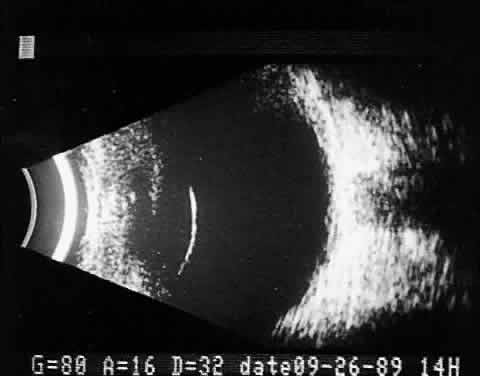

Real time refers to the display of motion or movement during B-scan imaging. This capability is one of the greatest advantages of B-scan. Differences in mobility of a variety of movable intraocular abnormalities can be easily detected. For example, the rapid movement of vitreous hemorrhage is usually easy to appreciate and differentiate from the slower, undulating movements of a recent, rhegmatogenous retinal detachment. On occasion, movement of intraocular structures can be used for detecting abnormalities that lie immediately behind vitreous opacification and may be seen only when the vitreous opacities are moved away from the ocular wall, set in motion by command voluntary movements of the patient's globe (Fig. 5). Gray scale refers to the variable gray tone of display screen echoes. Strong returning signals (echoes) appear white, whereas weaker reflections are seen as gray, the shade depending on echo strength. Examples of strong reflectors of sound include retinal tissue, sclera, and calcifications of any type (Fig. 6). Weaker echoes from clotted or clumped cells within the vitreous are usually easy to differentiate from the stronger reflectors of sound (Fig. 7). Grading of echo strength may be performed only when the examining ultrasound beam is perpendicular to the object of interest, ensuring the strongest possible reflections. However, in the world of ultrasound interpretation, there are many exception to the rules. Tissues that are usually mild reflectors of sound, such as hemorrhage, can at times appear quite strong, especially in complex or multiple pattern disorders, as frequently occur in severe ocular trauma. These apparent inconsistencies often cause misinterpretation by the novice. With experience obtained by multiple examinations, careful follow-up, and clinical correlation whenever possible, diagnostic acumen rapidly improves.

Fig. 5. Contact B-scans. A. Heavy formed vitreous hemorrhage obscuring choroidal mass. B. Voluntary movement of the globe causes the formed vitreous to shift, permitting easy detection of the ocular wall mass.